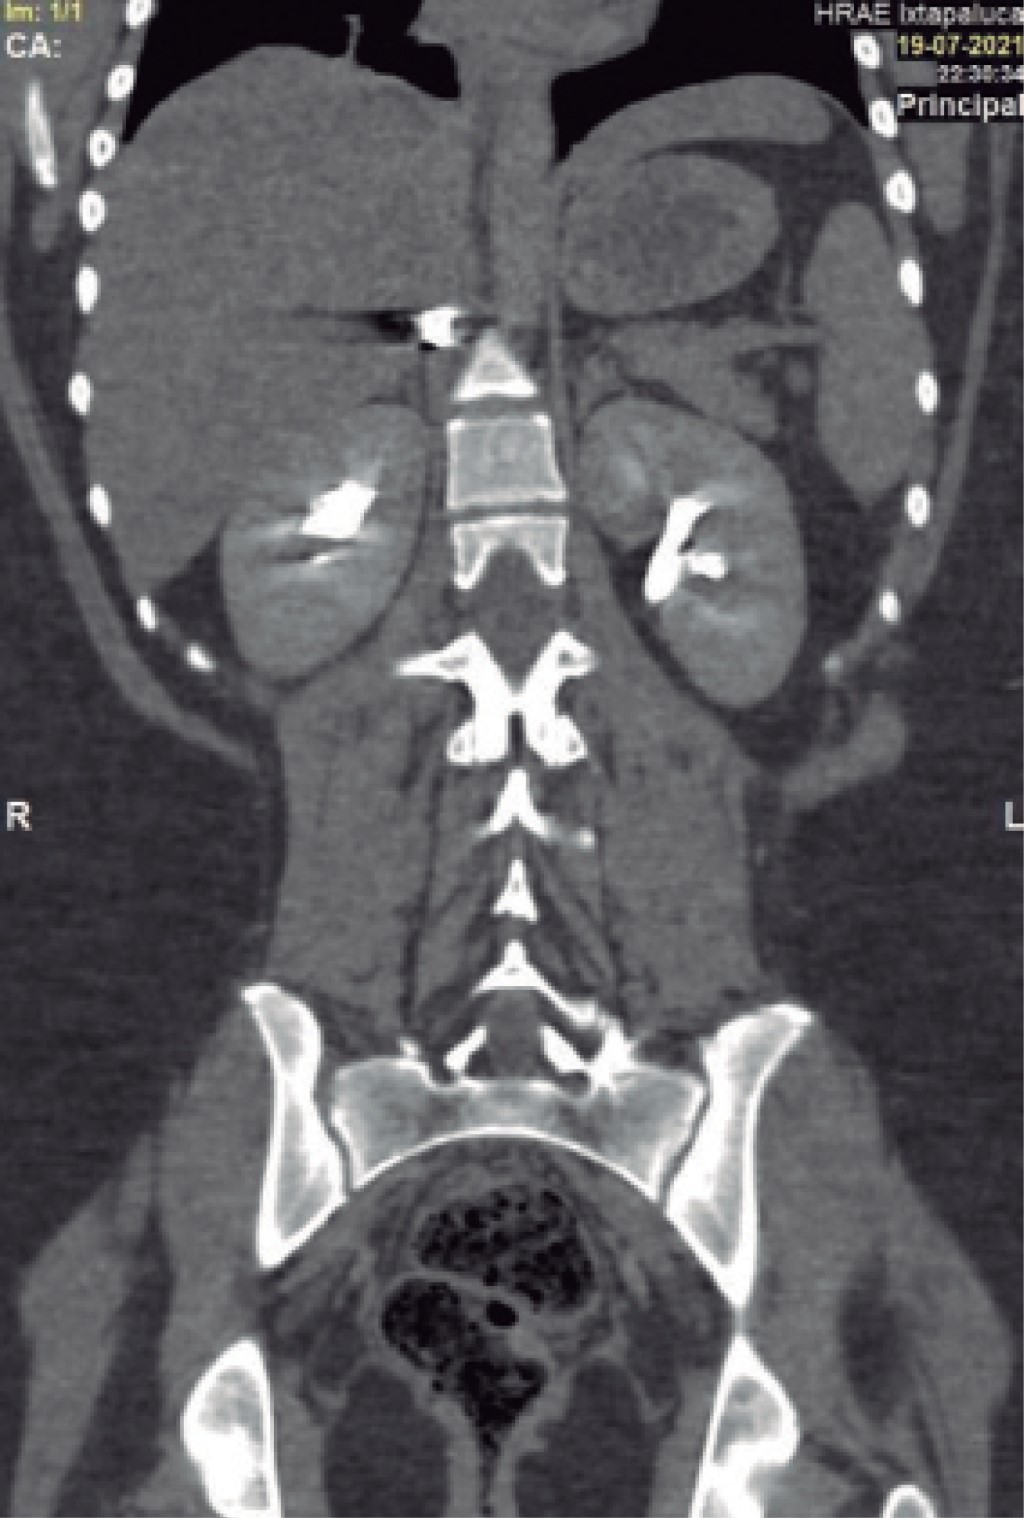

On physical examination, her vital signs were as follows: heart rate of 74 beats/minute; blood pressure of 98/67 mmHg; respiratory rate of 19/min; temperature of 36o C; and oxygen saturation of 98%. The chest showed a PAF entry orifice in the upper outer quadrant of the right breast (Figure 1), and the lung fields were well-ventilated. The abdomen was flat, with peristalsis, soft and painless to palpation. The blood cytology reported a hemoglobin of 12.8 g/dL, hematocrit of 36.4%, and white blood cells of 6,400/ml. The chest X-ray ruled out pneumothorax (Figure 2). A CT scan of the thorax and abdomen showed a metallic foreign body lodged in the right parasagittal line at the level of the 12th thoracic vertebra (Figure 3), without pulmonary or diaphragmatic lesion (Figures 4 and 5); in the abdomen, a PAF tract was observed with a 12 cm by 2.3 cm grade IV liver lesion in segments IV, VII and VIII of Couinaud (Figure 5), scarce free fluid, without lesion of any other organ (Figures 3, 5 and 6). Twenty-four hours later, a control CT scan was performed, showing the liver lesion without subcapsular collection or active extravasation on the application of contrast medium, without an increase of free fluid. Given the correlation of these findings with clinical stability, the patient was discharged on the fourth day of her admission. She did not have any complications one month after her discharge.